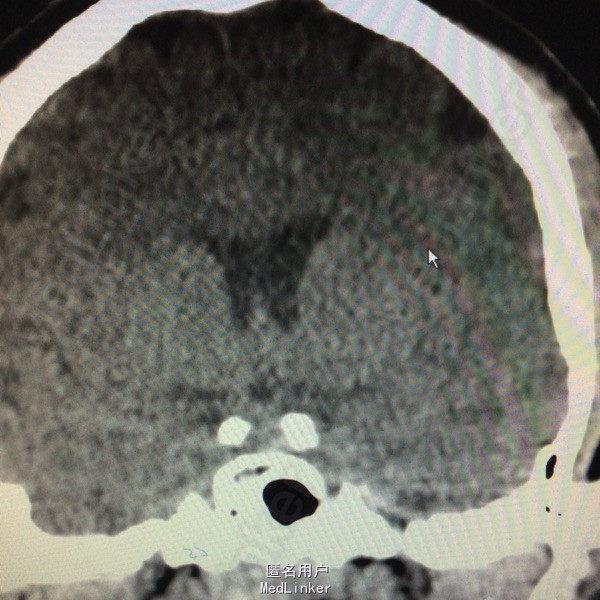

寰枕畸形:Arnold-Chiari畸形

主诉:行走不稳伴左下肢乏力1年余 病史:患者26岁男性,于1年前始出现左下肢乏力并进行性加重,外院行头颅CT检查提示:Arnold-Chiari畸形。

查体未见明显异常 头颅CT提示小脑扁桃体向下移位,延颈交界区脊髓受压,符合小脑扁桃体畸形

诊断:Arnold—Chiari畸形。 治疗:行寰枕畸形减压术,将枕骨大孔及环椎减压。

随访:患者恢复良好出院 讨论:Arnold-Chiari畸形又称小脑扁桃体下疝畸形,是小脑扁桃体经枕骨大孔疝入至颈椎管内形成的先天性畸形,多伴发脑积水、脊柱裂及脊髓脊膜膨出、脊髓空洞症等多种先天性畸形。 该病人出现明显一侧肢体乏力,